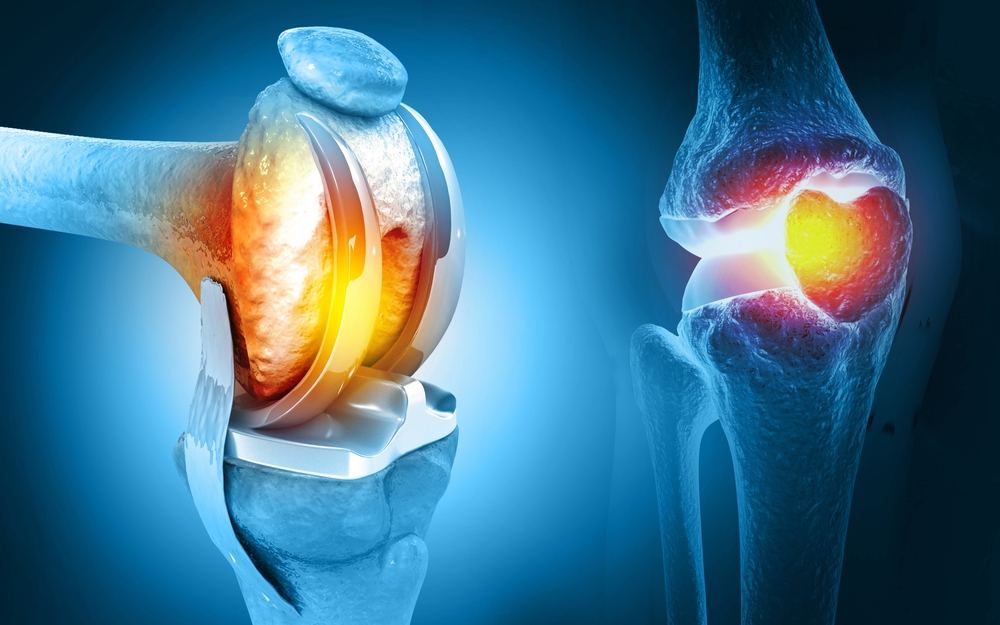

Orthopedics & joints replacement surgery